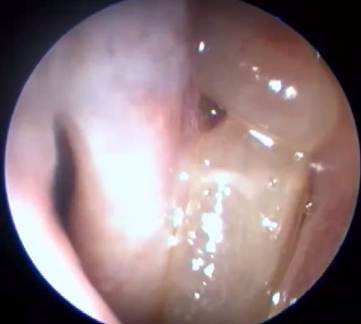

Vänster näsborre, konka media i mitten sinus maxillaris till höger

Bra veta, kommer vi längre bak når vi koanen innan vi når? Där vad hos barn brukar sitta?

A

Epifarynx (nässvalg) där adenoid hos barn sitter